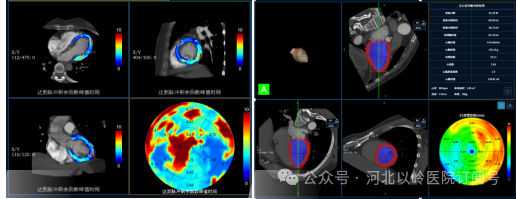

缺血性心脏病一站式检查

缺血性心脏病一站式CT检查可以可通过一次打药、一次扫描以及图像重建,同时获得心肌灌注参数、冠状动脉图像及心功能分析。正确评价冠状动脉有无狭窄、心肌供血情况,冠状动脉狭窄程度与心肌供血关系等。